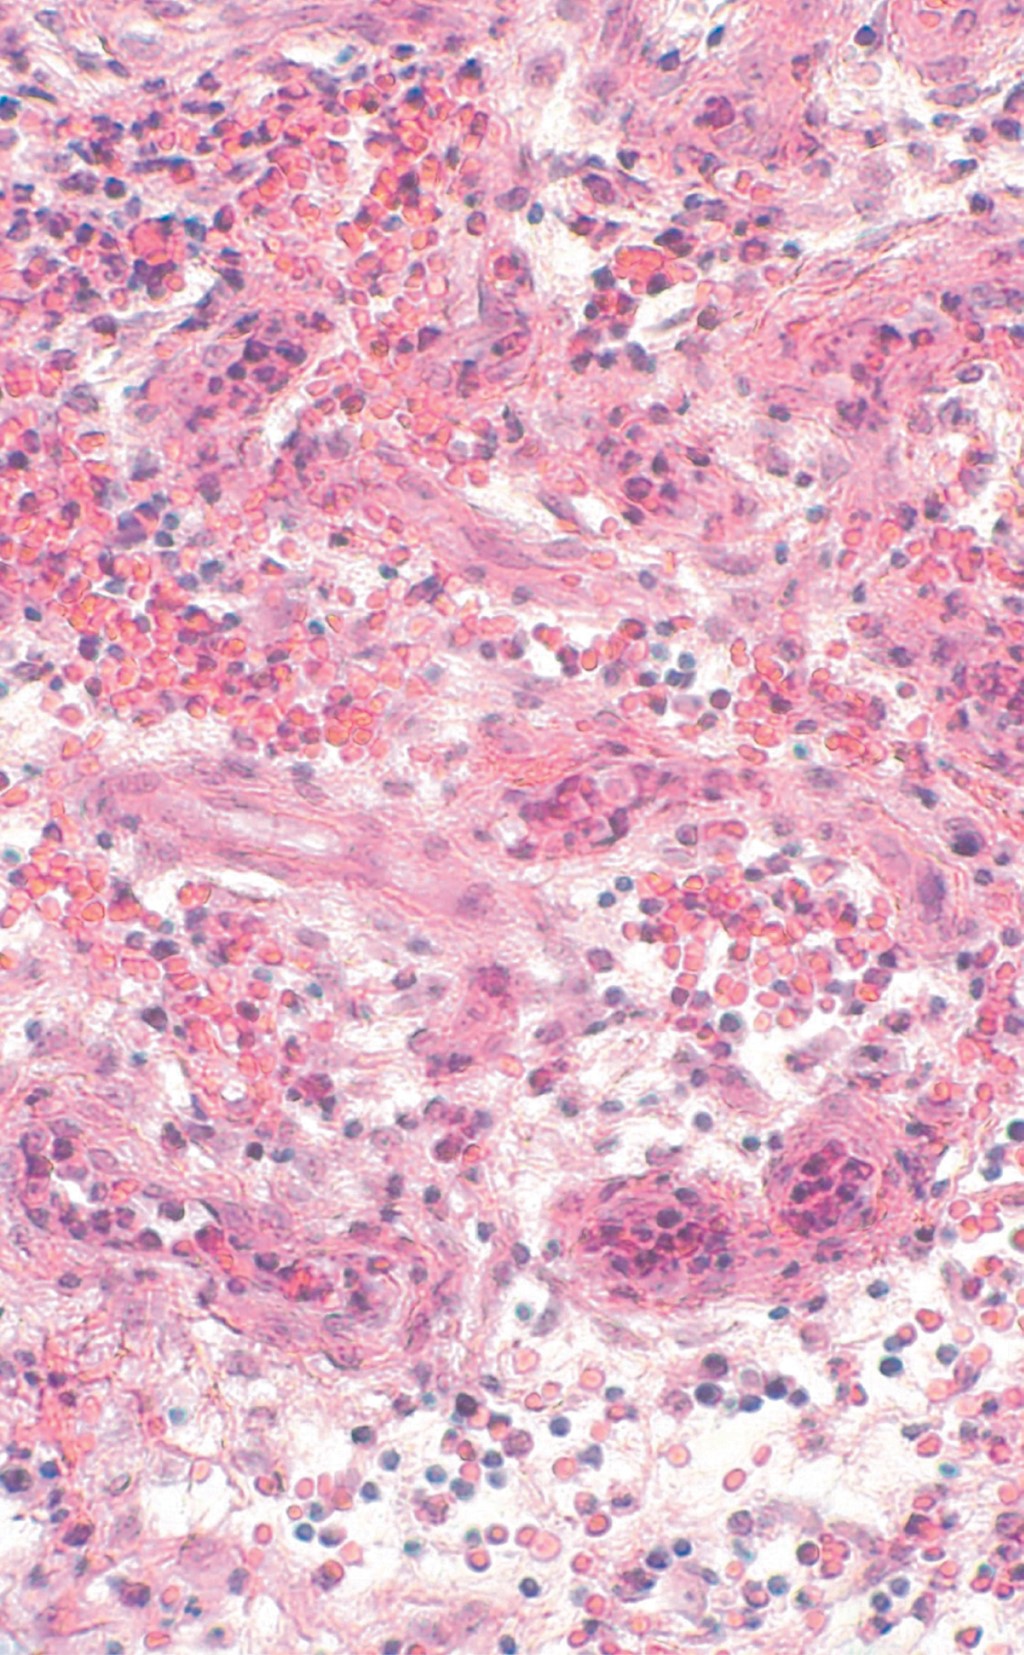

Los hallazgos histopatológicos no son característicos de PG; en las lesiones iniciales aparece una reacción vascular neutrofílica que puede ser foliculocéntrica. Los infiltrados neutrofílicos se observan en las lesiones activas, con necrosis central, ulceración de la epidermis y escaso infiltrado mononuclear más periférico, engrosamiento del endotelio capilar, hemorragia y coagulación. Los hallazgos histopatológicos también dependen del sitio de la biopsia (borde, centro o área necrótica de la úlcera), el estadio de progresión y la variedad de la enfermedad (vegetante, ampollosa, ulcerosa o pustulosa).8

Entre sus antecedentes patológicos refirió artritis reumatoide sin tratamiento de ocho años de evolución, tabaquismo con índice tabáquico de 3.75 y alcoholismo positivo a razón de 10 copas semanales hasta llegar a la embriaguez. Se solicitan estudios de laboratorio generales sin encontrarse datos relevantes, el factor reumatoide fue de 9.6. Dentro del protocolo de estudio se realizó una biopsia incisional de piel para estudio histopatológico, el cual mostró la epidermis con acantosis regular, zonas con hiperplasia pseudoepiteliomatosa, amplias zonas ulceradas. La dermis superficial, media y profunda mostró infiltrados moderadamente densos con participación de histiocitos, células gigantes multinucleadas de tipo cuerpo extraño, así como numerosos polimorfonucleares dentro y fuera de los vasos; amplias zonas de fibrosis de la colágena y focos con extravasación de eritrocitos (Figuras 5, 6 y 7).